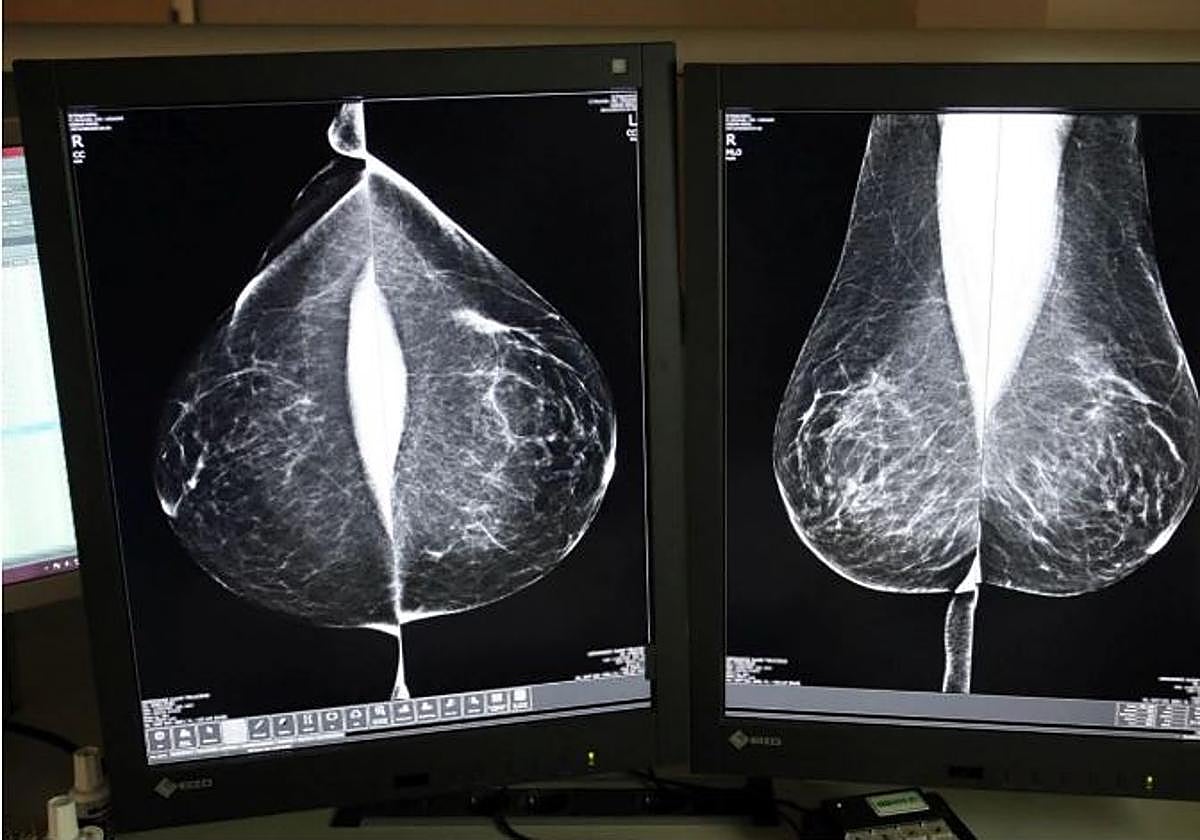

Mamografía para detectar un posible daño.

La Junta de Castilla y León defendió hoy que gestiona con la «mayor celeridad posible» las segundas pruebas que se prescriben a las mujeres cuyas mamografías en los programas de cribado de cáncer de mama no descartan la existencia de lesiones o presentan factores de riesgo, mientras que en los casos positivos se ofrecen los tratamientos y terapias de forma directa. Además, en los casos negativos, son los médicos de Atención Primaria los que informan con «mucha» rapidez a las pacientes.